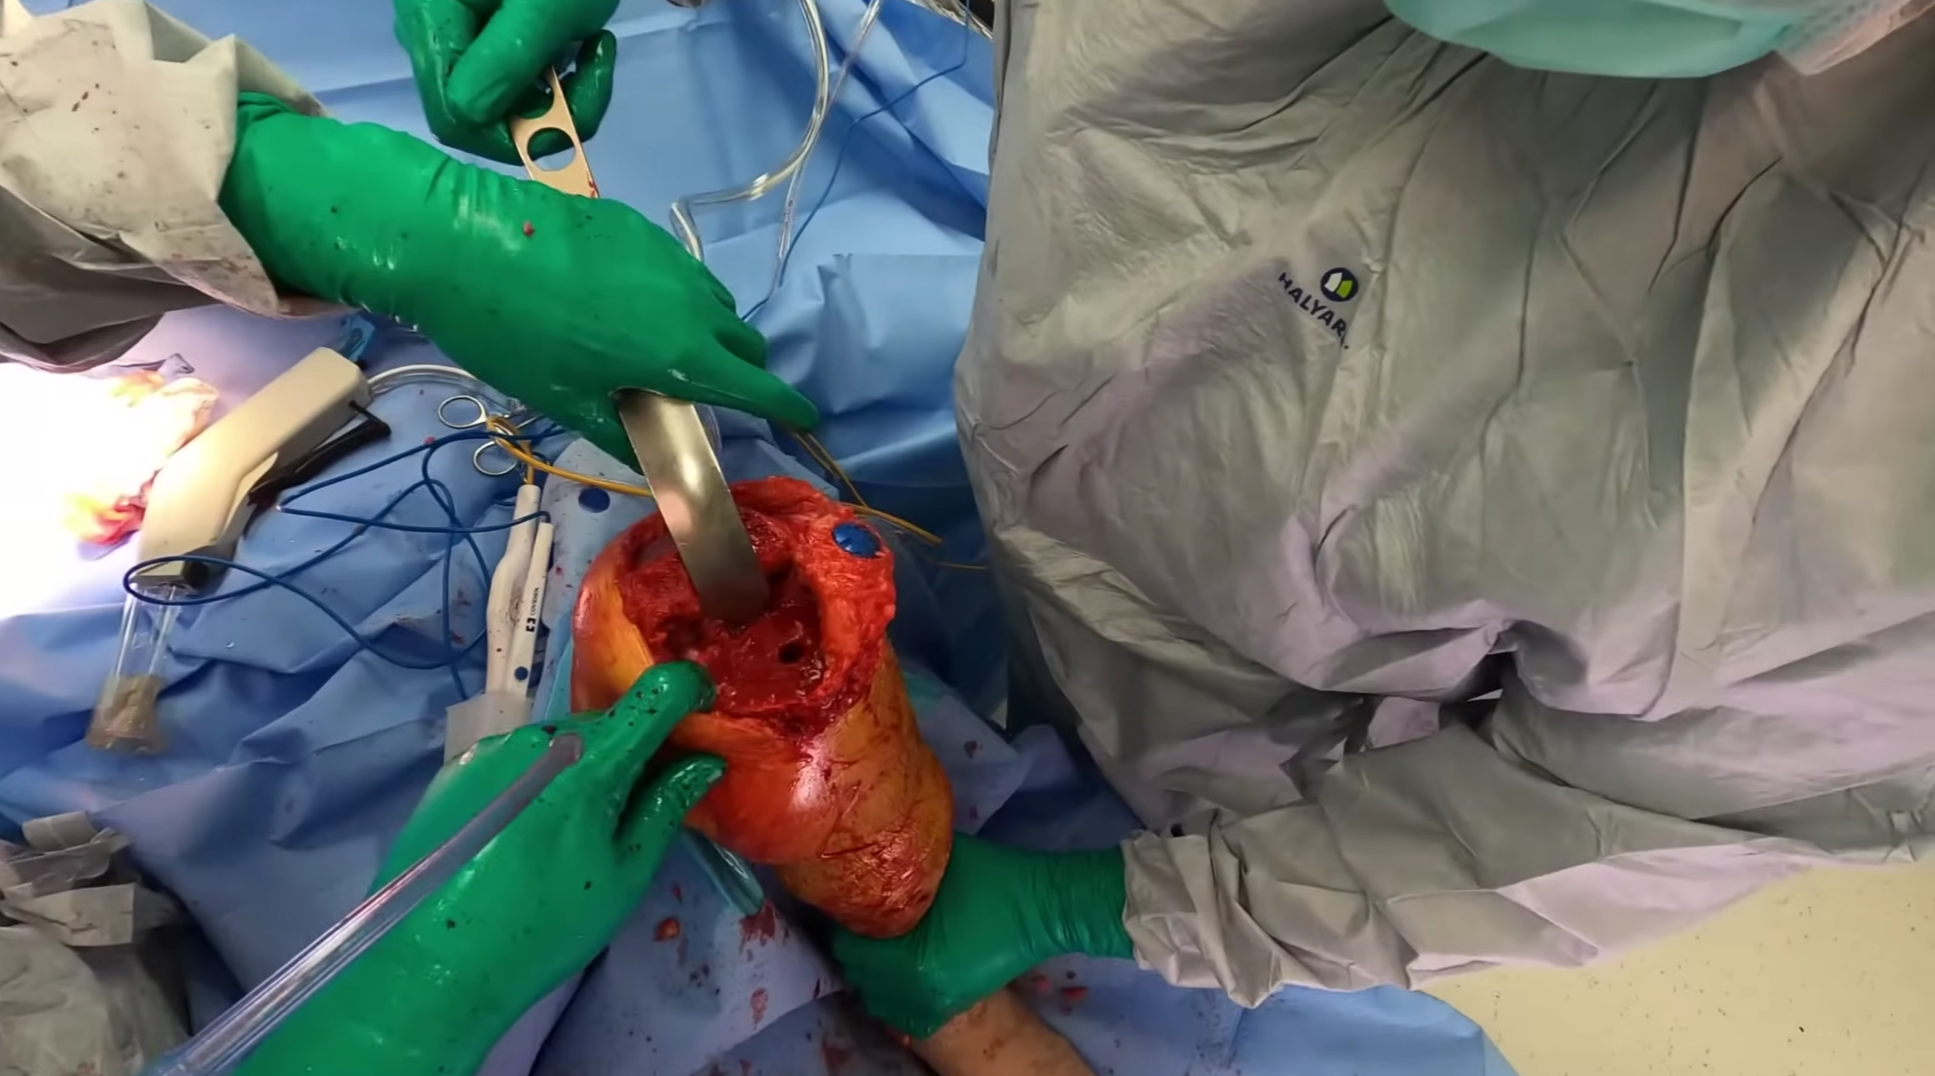

Cilt Grefti Uygulaması

Cilt Grefti Uygulaması

Cilt Grefti Uygulaması